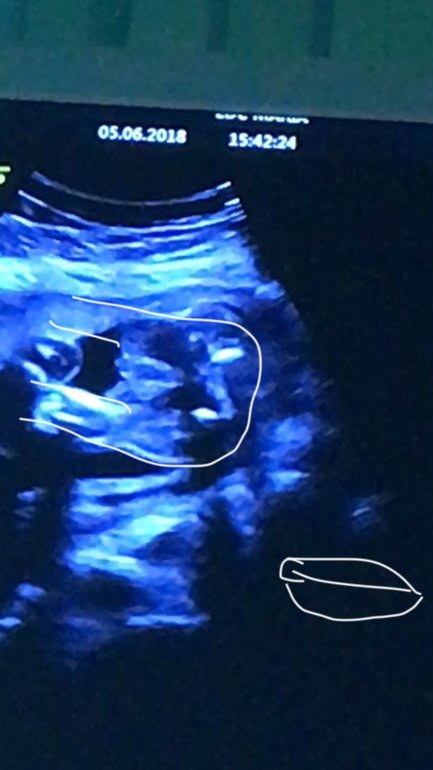

Узи. 22нед МАЛЬЧИК или ДЕВОЧКА?

Пол малышаНа стоп кадрах узи есть и пирожок и перчик🤣

Я делала на тел запись при узи и прям по секундам его пересмотрела, и что вы думаете.... с разницей в полсекунды там и пирожок и писюн🤷♀️

Смотрите сами) кто что видит???